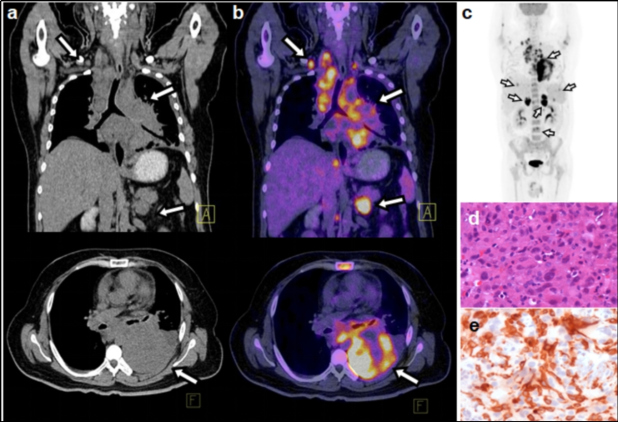

El ID calculado considerando los pacientes con etiología maligna confirmada mediante biopsia o seguimiento, arrojó un valor de 47%. La proporción de FP tomando en cuenta aquellos pacientes con al menos un hallazgo positivo en el PET-CT con otra etiología confirmada que no fuera maligna y aquellos en los cuales no fue posible determinar el tipo de etiología mediante biopsia o seguimiento, fue de 27%. De los pacientes en los que se encontró una etiología maligna, 49 casos fueron confirmados mediante biopsia y 1 mediante seguimiento. De los pacientes con biopsia, el diagnóstico de anatomía patológica más frecuente fue el adenocarcinoma pobremente diferenciado (tabla 1). En cuanto a localización, el sitio primario más común fue el pulmón, seguido del páncreas (tabla 2). Las figuras 1-4 ilustran algunos casos representativos de nuestra serie.